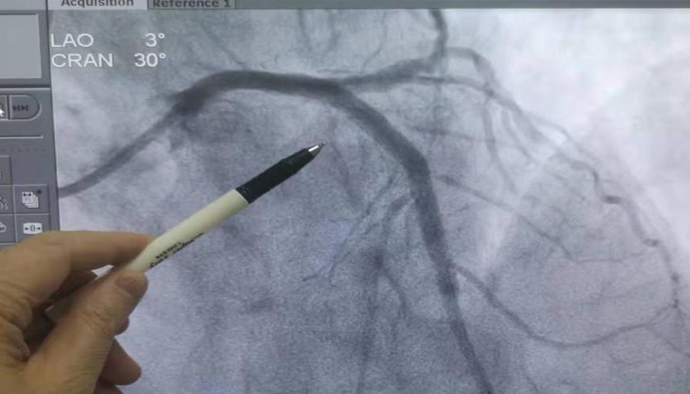

心臟血管閉塞(術(shù)前)圖示

2022年11月15日,西藏阜康醫(yī)院心血管內(nèi)科門診接診了一名患者,患者主訴胸悶、胸痛4小時(shí)。通過(guò)心電圖檢查,檢查結(jié)果顯示:急性心肌梗塞(廣泛性前壁)。

接診醫(yī)生為患者及患者家屬交代了病情的危險(xiǎn)性及預(yù)后等情況后,經(jīng)患者及患者家屬同意,按急性胸痛管理流程處理,立即送往心血管介入造影導(dǎo)管室行急救手術(shù),術(shù)后患者安全返回病房。